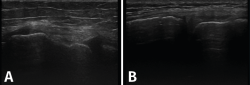

Ecografía

El ultrasonido se puede usar en el diagnóstico de numerosas patologías y puede guiar en procedimientos diagnósticos y terapéuticos(5).

Su indicación fundamental es en el diagnóstico de las lesiones de partes blandas superficiales.

Las estructuras específicas más adecuadas para este estudio incluyen tendones, músculos y ligamentos, además de masas periarticulares de tejidos blandos. Es útil para el diagnóstico de derrame articular, engrosamiento sinovial, bursitis, cuerpos libres intraarticulares, gangliones, quistes, roturas ligamentosas y tendinosas, tendinitis y fracturas ocultas(6).

En el estudio musculoesquelético se utiliza una sonda lineal con alta frecuencia, de entre 9 y 13 mHz.

1. Ligamentos

Tanto el ligamento lateral interno (LLI) como el ligamento lateral externo (LLE) pueden ser valorados por ecografía (Figura 7).

Figura 7. Corte coronal de una ecografía de rodilla. A: engrosamiento del ligamento lateral externo en la inserción proximal por un esguince de grado I; B: engrosamiento del ligamento lateral interno.